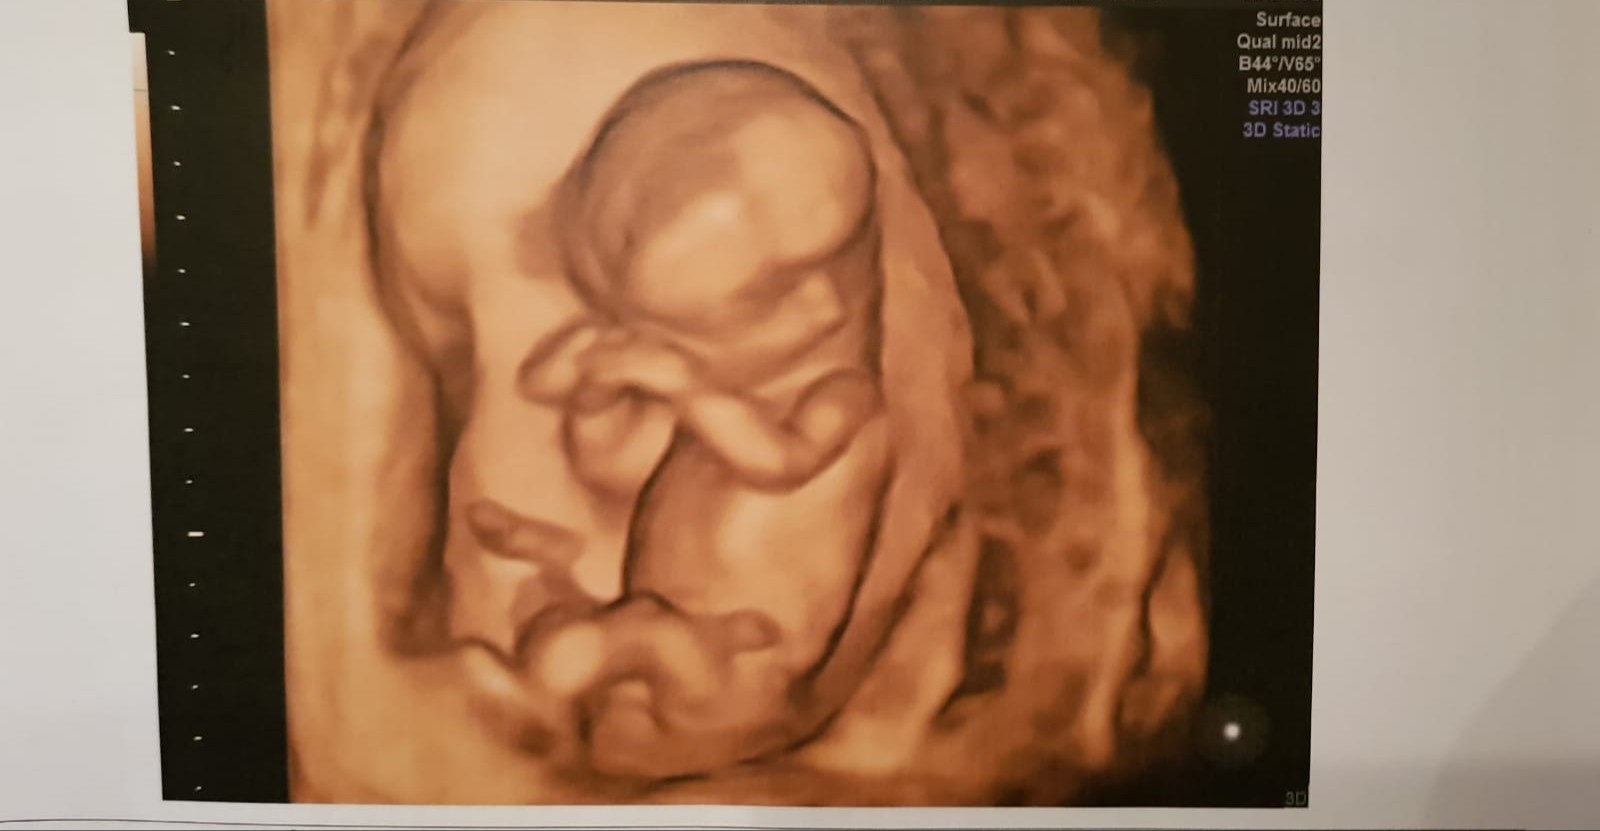

Metoda ramzi do 8tyg. Też dziewczynka

Metoda nub czyli analiza wyrostka pluciowego do 14tc - CHLOPCZYK